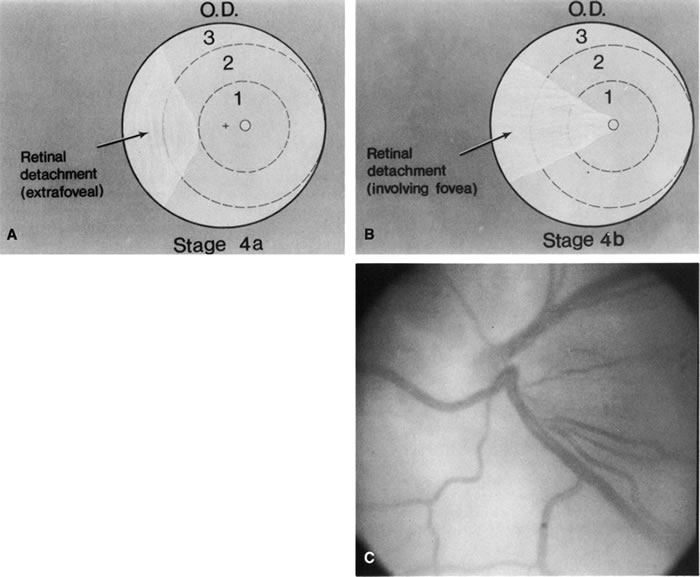

The indications for scleral buckling surgery are stage 4A with progression, stage 4B or open funnel stage 5 retinal detachment. Stage 4A retinal detachment (Fig. 7A) is subtotal, and spares the fovea. The CryoROP study demonstrated resolution in 46.1% of eyes with stage 4A retinal detachments at 4½ years. 61 Unfortunately, the study also showed a 17.9% risk of progression for stage 4A eyes to total retinal detachment. Stage 4B retinal detachment (Fig. 7B), which is due to progressive exudation or traction, involves detachment of the fovea. Stage 5 retinal detachment (Fig. 7C) is total; it may have an open or closed funnel configuration. When the detachment is funnel shaped, the funnel is divided into anterior and posterior parts, and may be open or closed in either location.

Fig. 7. A. Stage 4A ROP. Subtotal retinal detachment does not involve the fovea. B. Stage 4B ROP. Subtotal retinal detachment involves the fovea. C. Stage 5 ROP. Total retinal detachment. The detachment may be shallow, with an open funnel configuration, as in this example. Note the loss of the choroidal vascular pattern because of subretinal fluid.